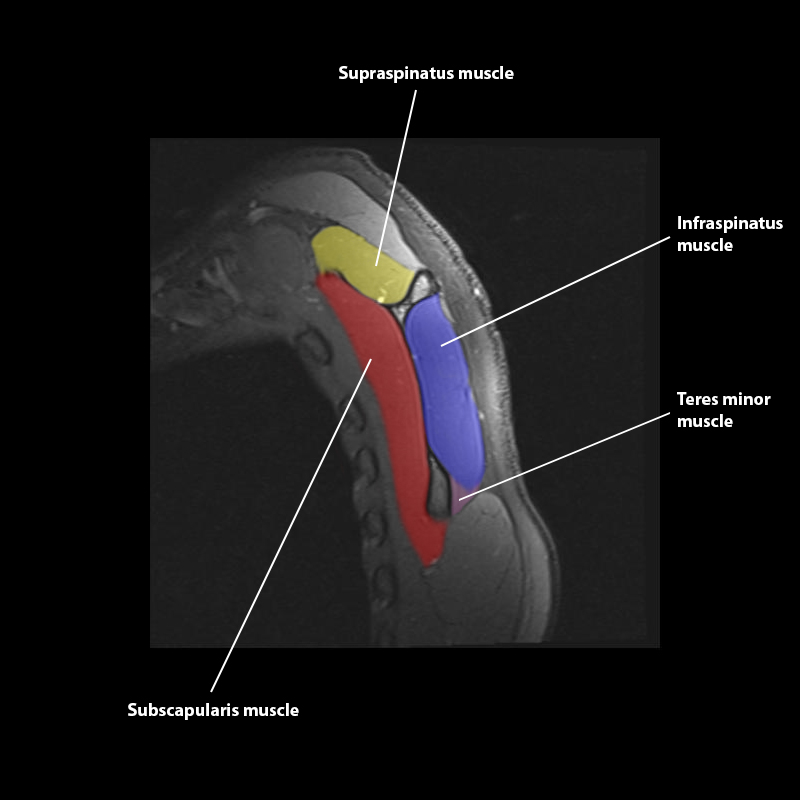

Shoulder MRI Anatomy